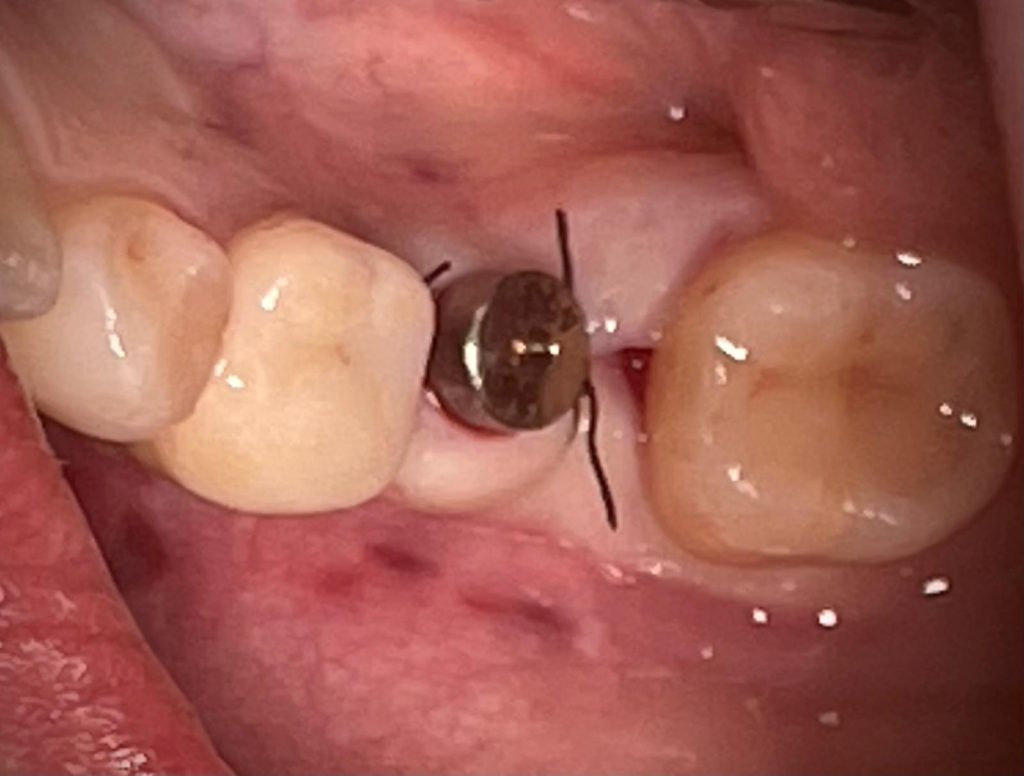

In questo caso specifico, con l’impianto PRAMA di Sweden&Martina è possibile gestire il posizionamento in senso apico-coronale per poter tenere la connessione impianto/abutment sovracrestale; in questo modo è possibile tenere l’eventuale infiltrato batterico lontano dal tessuto osseo.

Ne deriva un miglior risultato nel tempo e si riduce il rischio di perimplantiti.